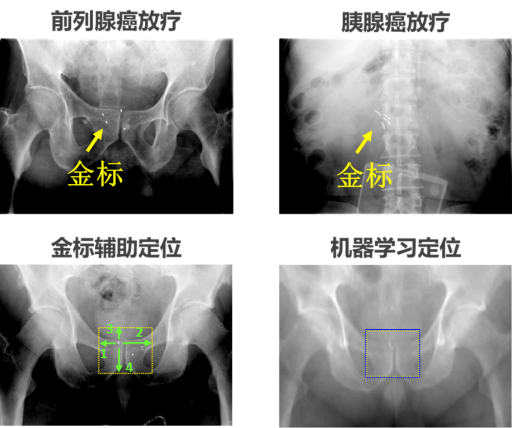

图2. 图像引导放疗